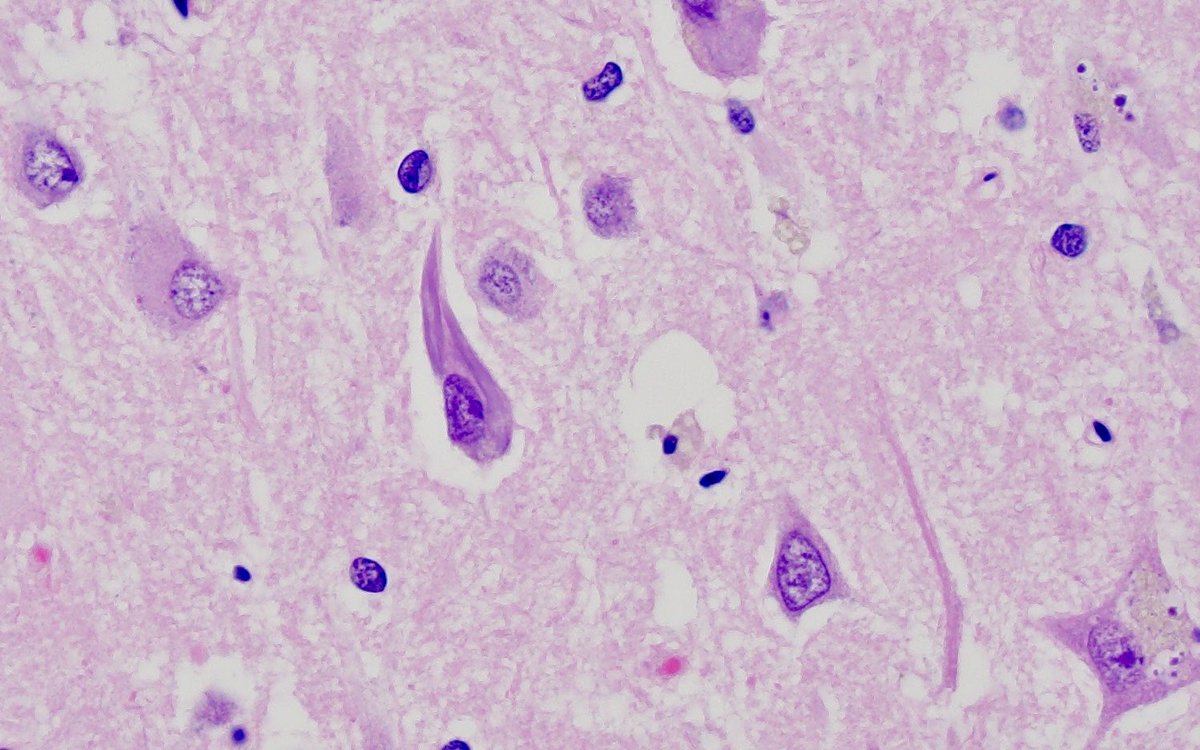

What pathologies can be seen in these two photos? In what clinical scenario are these changes typically observed? #neuropath 🧠🔬

9

28

121